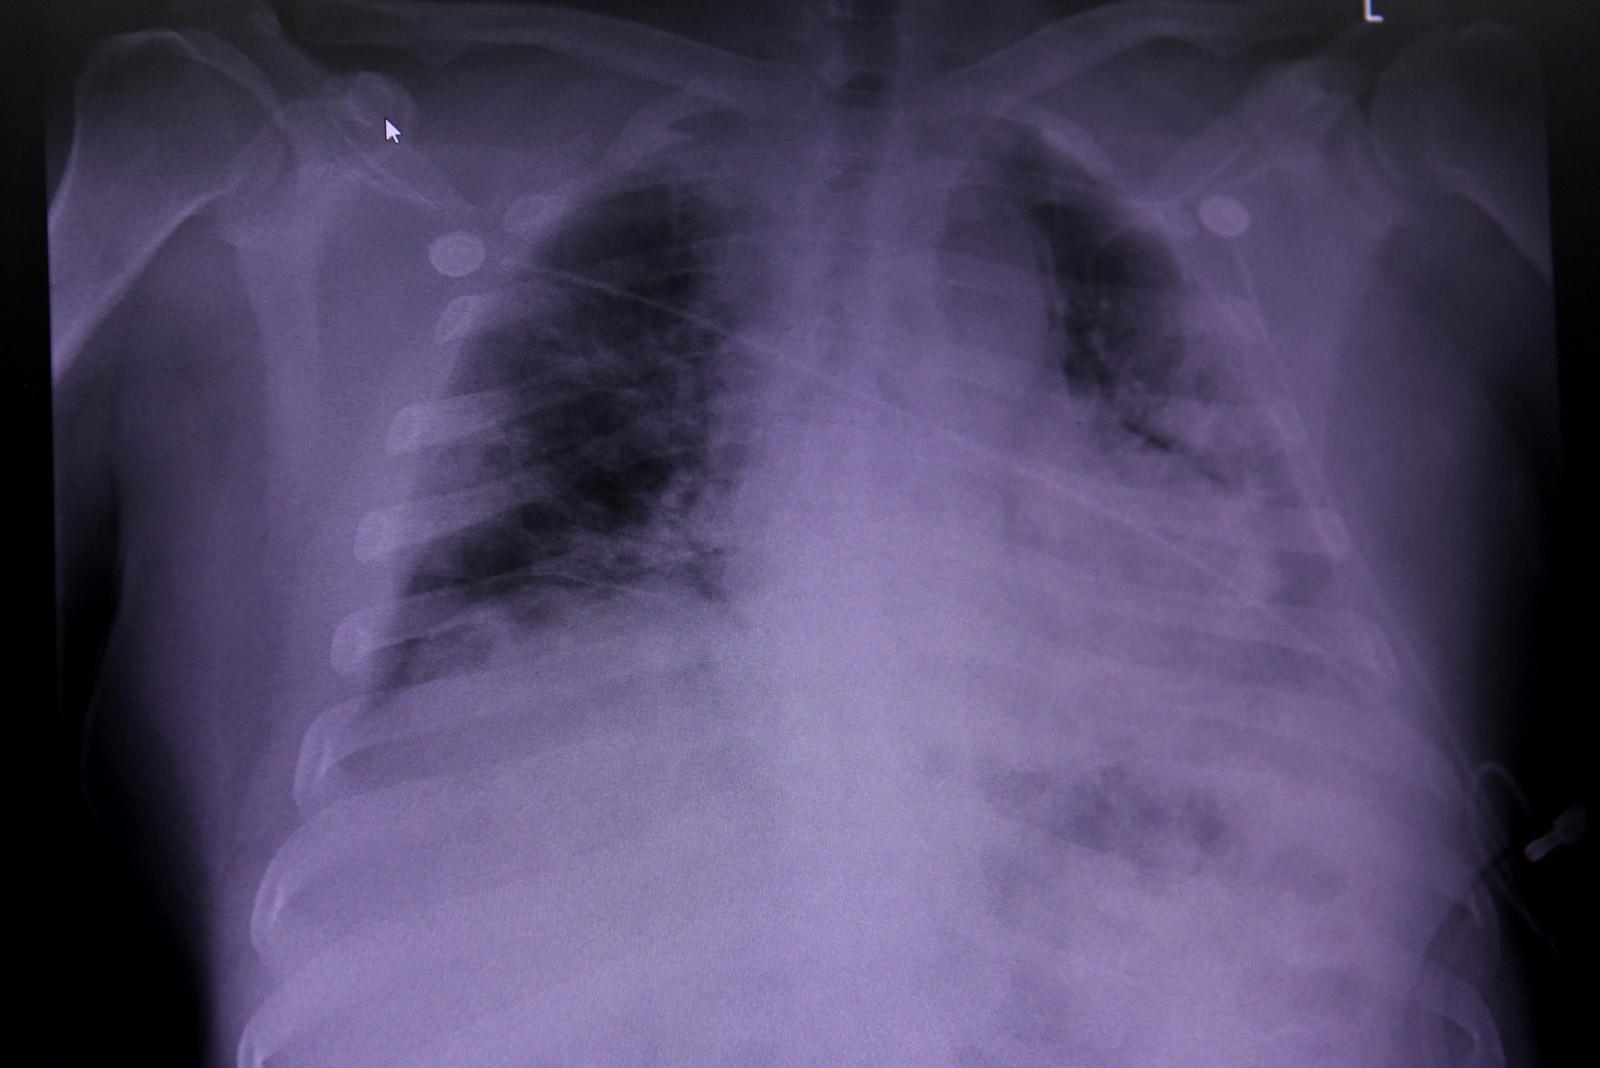

Στις αρχές του φετινού έτους, μελέτη που πραγματοποιήθηκε στη Γουχάν της Κίνας έδειξε ότι 1.700 πρώην ασθενείς του κορωνοϊού είχαν υποστεί μικρότερες ή μεγαλύτερες, μόνιμες βλάβες στους πνεύμονές τους, όπως φάνηκε από τις ακτινογραφίες τους.